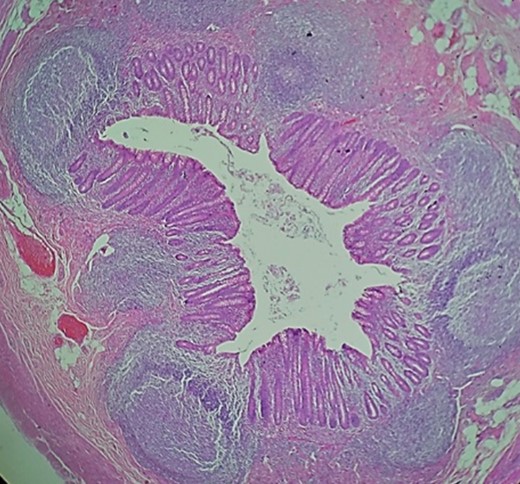

Intravenous antibiotics were commenced preoperatively and a Mcburney incision was made, multiple adhesions were found near the cecum, and the cecum wall appeared hyperemic with intense inflammation near the base of the appendix. After blunt dissection, two 3 cm toothpicks were discovered, one that perforated the appendix wall near its base and another one that jeopardized the cecum wall (Figs 1–3).

Hyperemic cecum wall with intense inflammation near the base of the appendix.

Transoperative image of the cecum and appendix with the two toothpicks.